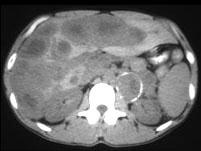

问题 男,37岁,阵发性高血压1个月余,请结合所提供图像,选择最佳答案 ( )

选项 A、肝转移瘤 B、原发性肝癌 C、左侧恶性嗜铬细胞瘤 D、左侧肾上腺转移瘤 E、左侧肾上腺癌

答案 AC